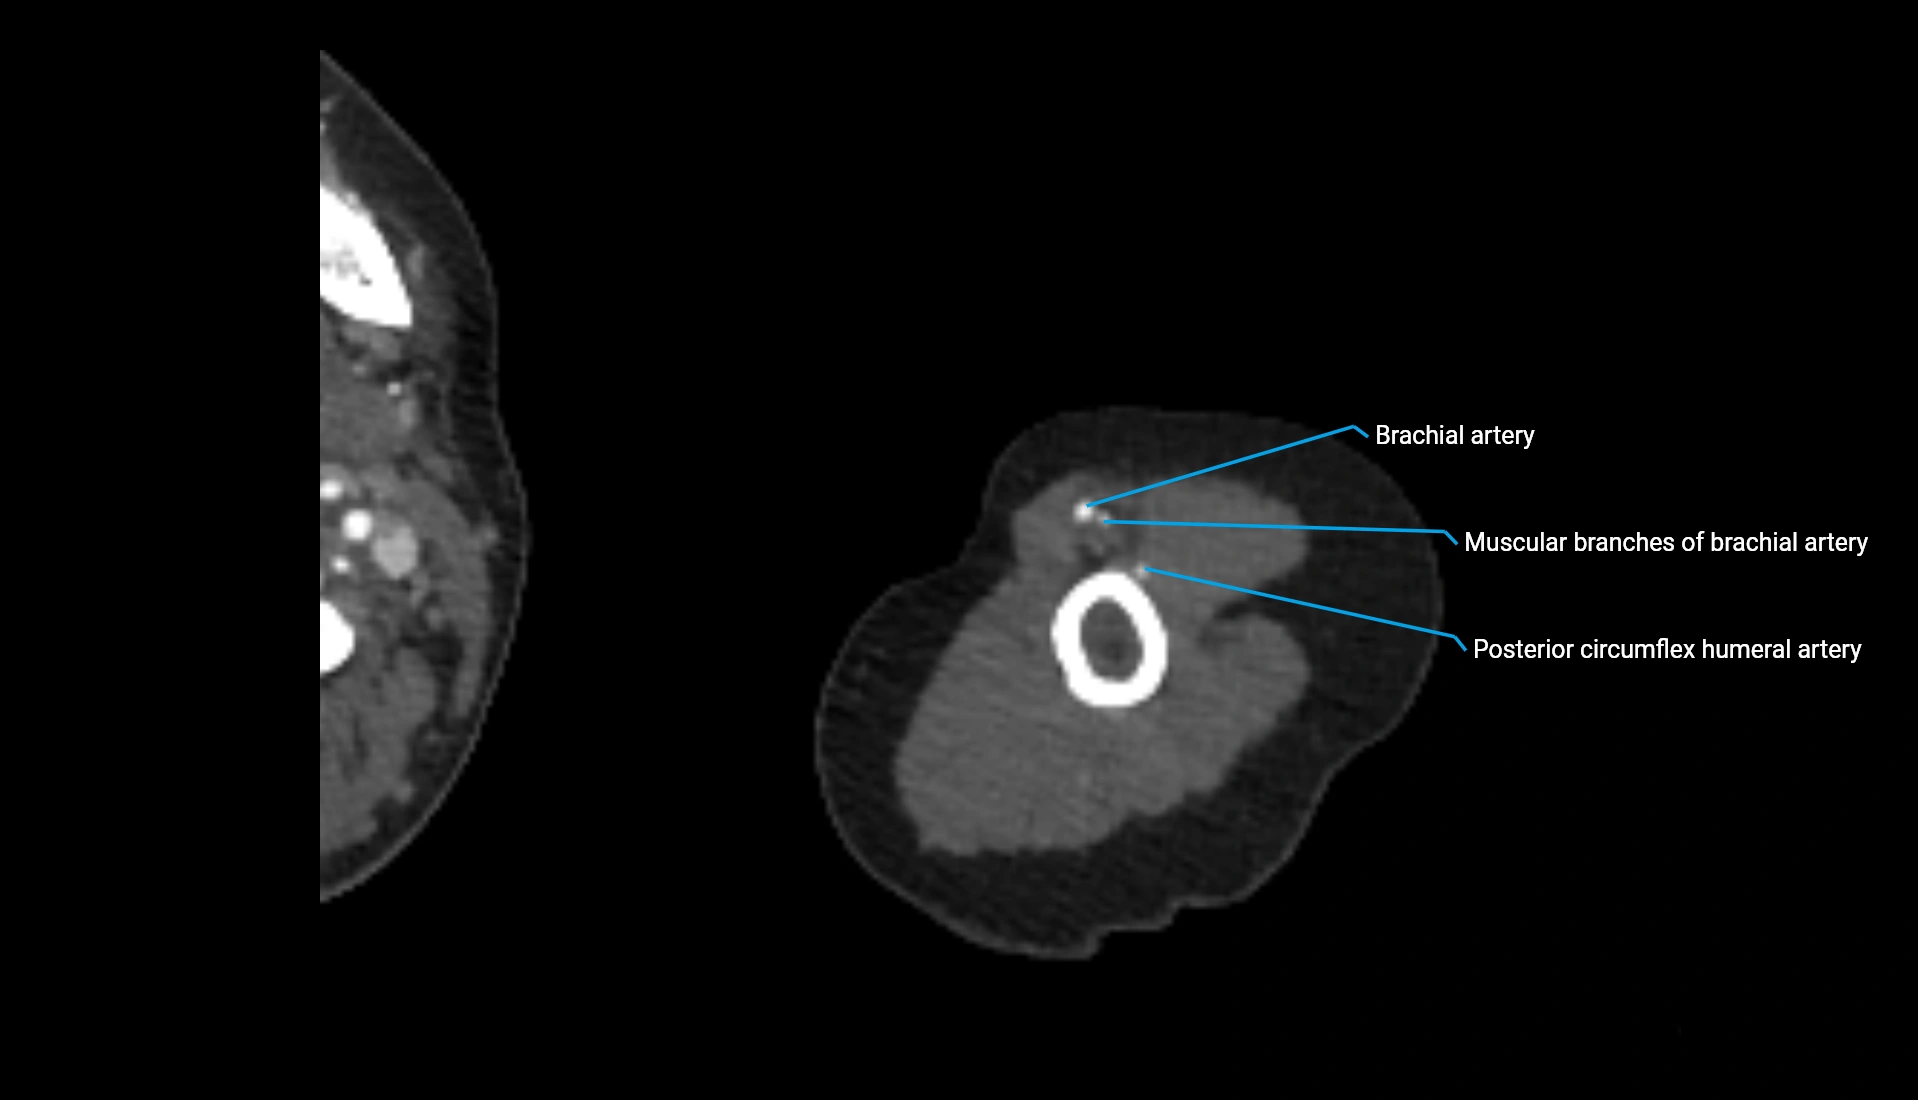

CT Appearance

Non-Contrast CT:

• Cortex: High-density, sharply defined

• Subchondral bone: Dense cancellous matrix

• Articular surface: Smooth concave contour articulating with the capitellum

• Excellent for evaluating bone integrity, alignment, and subtle fractures

Post-Contrast CT:

• Bone: No enhancement

• Joint capsule and synovium: Mild enhancement outlining the joint

• Improves contrast between soft tissues and bony margins

• Useful in detecting subtle joint abnormalities or postoperative changes